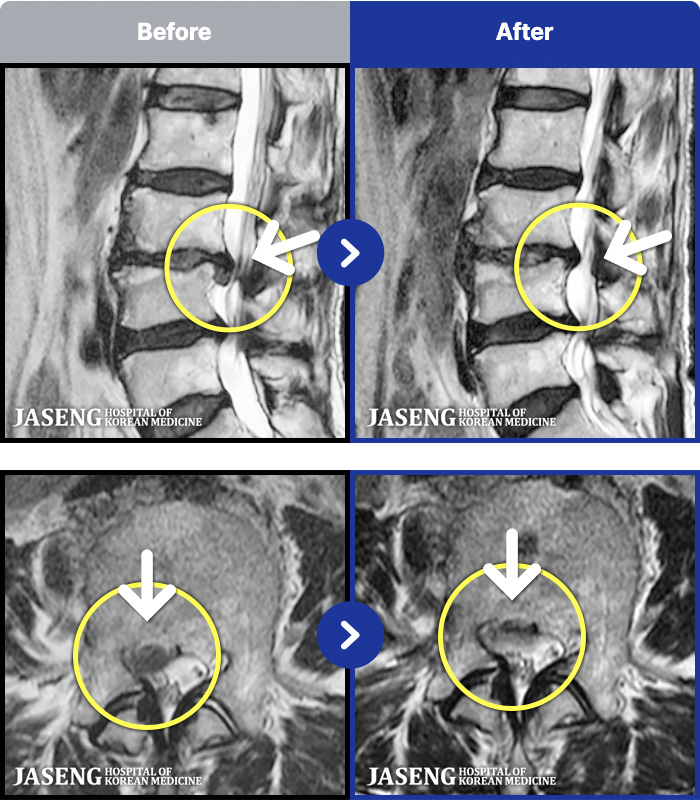

188 MRI ũ ʸ Ȯϼ.

ȯںп Ǹ ǿ ԿǾ, ο ġ ۿ Ƿ ġḦ Ͻñ ٶϴ.